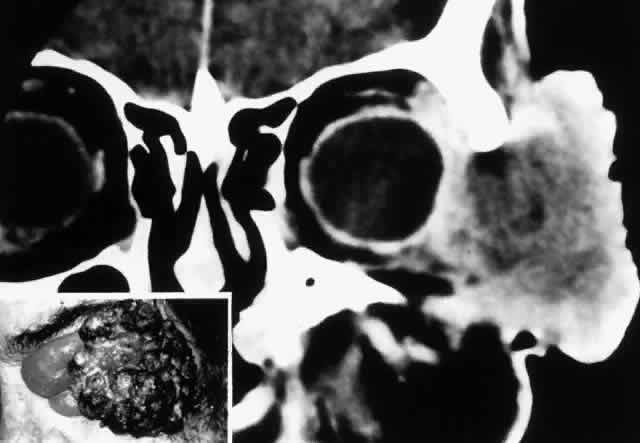

Fig. 7. A 61-year-old chronic alcoholic man presented with a fungating, putrefying, left temporal mass(inset) that extended into the adjacent orbit and flattened the globe, as shown on coronal CT scan. It proved to be a squamous cell carcinoma of the skin associated with cervical and mediastinal adenopathy. He underwent radical local radiotherapy, which led to regression of the local lesion. (Rootman J, Ragaz J, Cline R, Lapointe JS: Metastatic and secondary tumors of the orbit. In Rootman JR (ed): Diseases of the Orbit: A Multidisciplinary Approach, pp 405–427. Philadelphia, JB Lippincott, 1988.)